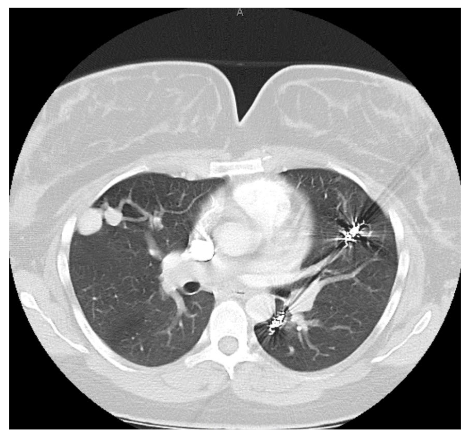

The recommended imaging studies were significant for numerous bilateral PAVM and she underwent placement of 10 total vascular coils antenatally. Unfortunately, the largest PAVM measured 32mm and was located within the left lingula, where a feeding vessel could not be identified. The next largest PAVM measured 17 mm (located in the right lower lobe) and 23 mm (located in the right upper lobe), both of which were successfully treated.

On postpartum day 1, the patient experienced an episode of acute onset hemoptysis, oxygen desaturation, tachycardia, and tachypnea. Prompt laboratory and imaging studies were obtained and pulmonology, anesthesia, and high-risk obstetrics were consulted. The patient immediately returned to the ICU where she was intubated due to persistent hypoxia. Repeat chest imaging was consistent with pulmonary hemorrhage. This was managed with urgent PAVM embolization, at which time a total of 4 vascular coils were placed in a right lower lobe PAVM that measured 17 mm. Notably, this was not one of the larger PAVMs targeted during antenatal embolization. The patient was subsequently extubated on postpartum day 3 and returned to the postpartum floor on postpartum day 4. The remainder of her hospital course was unremarkable and she was discharged home on postpartum day 5 in stable condition with appropriate follow up.